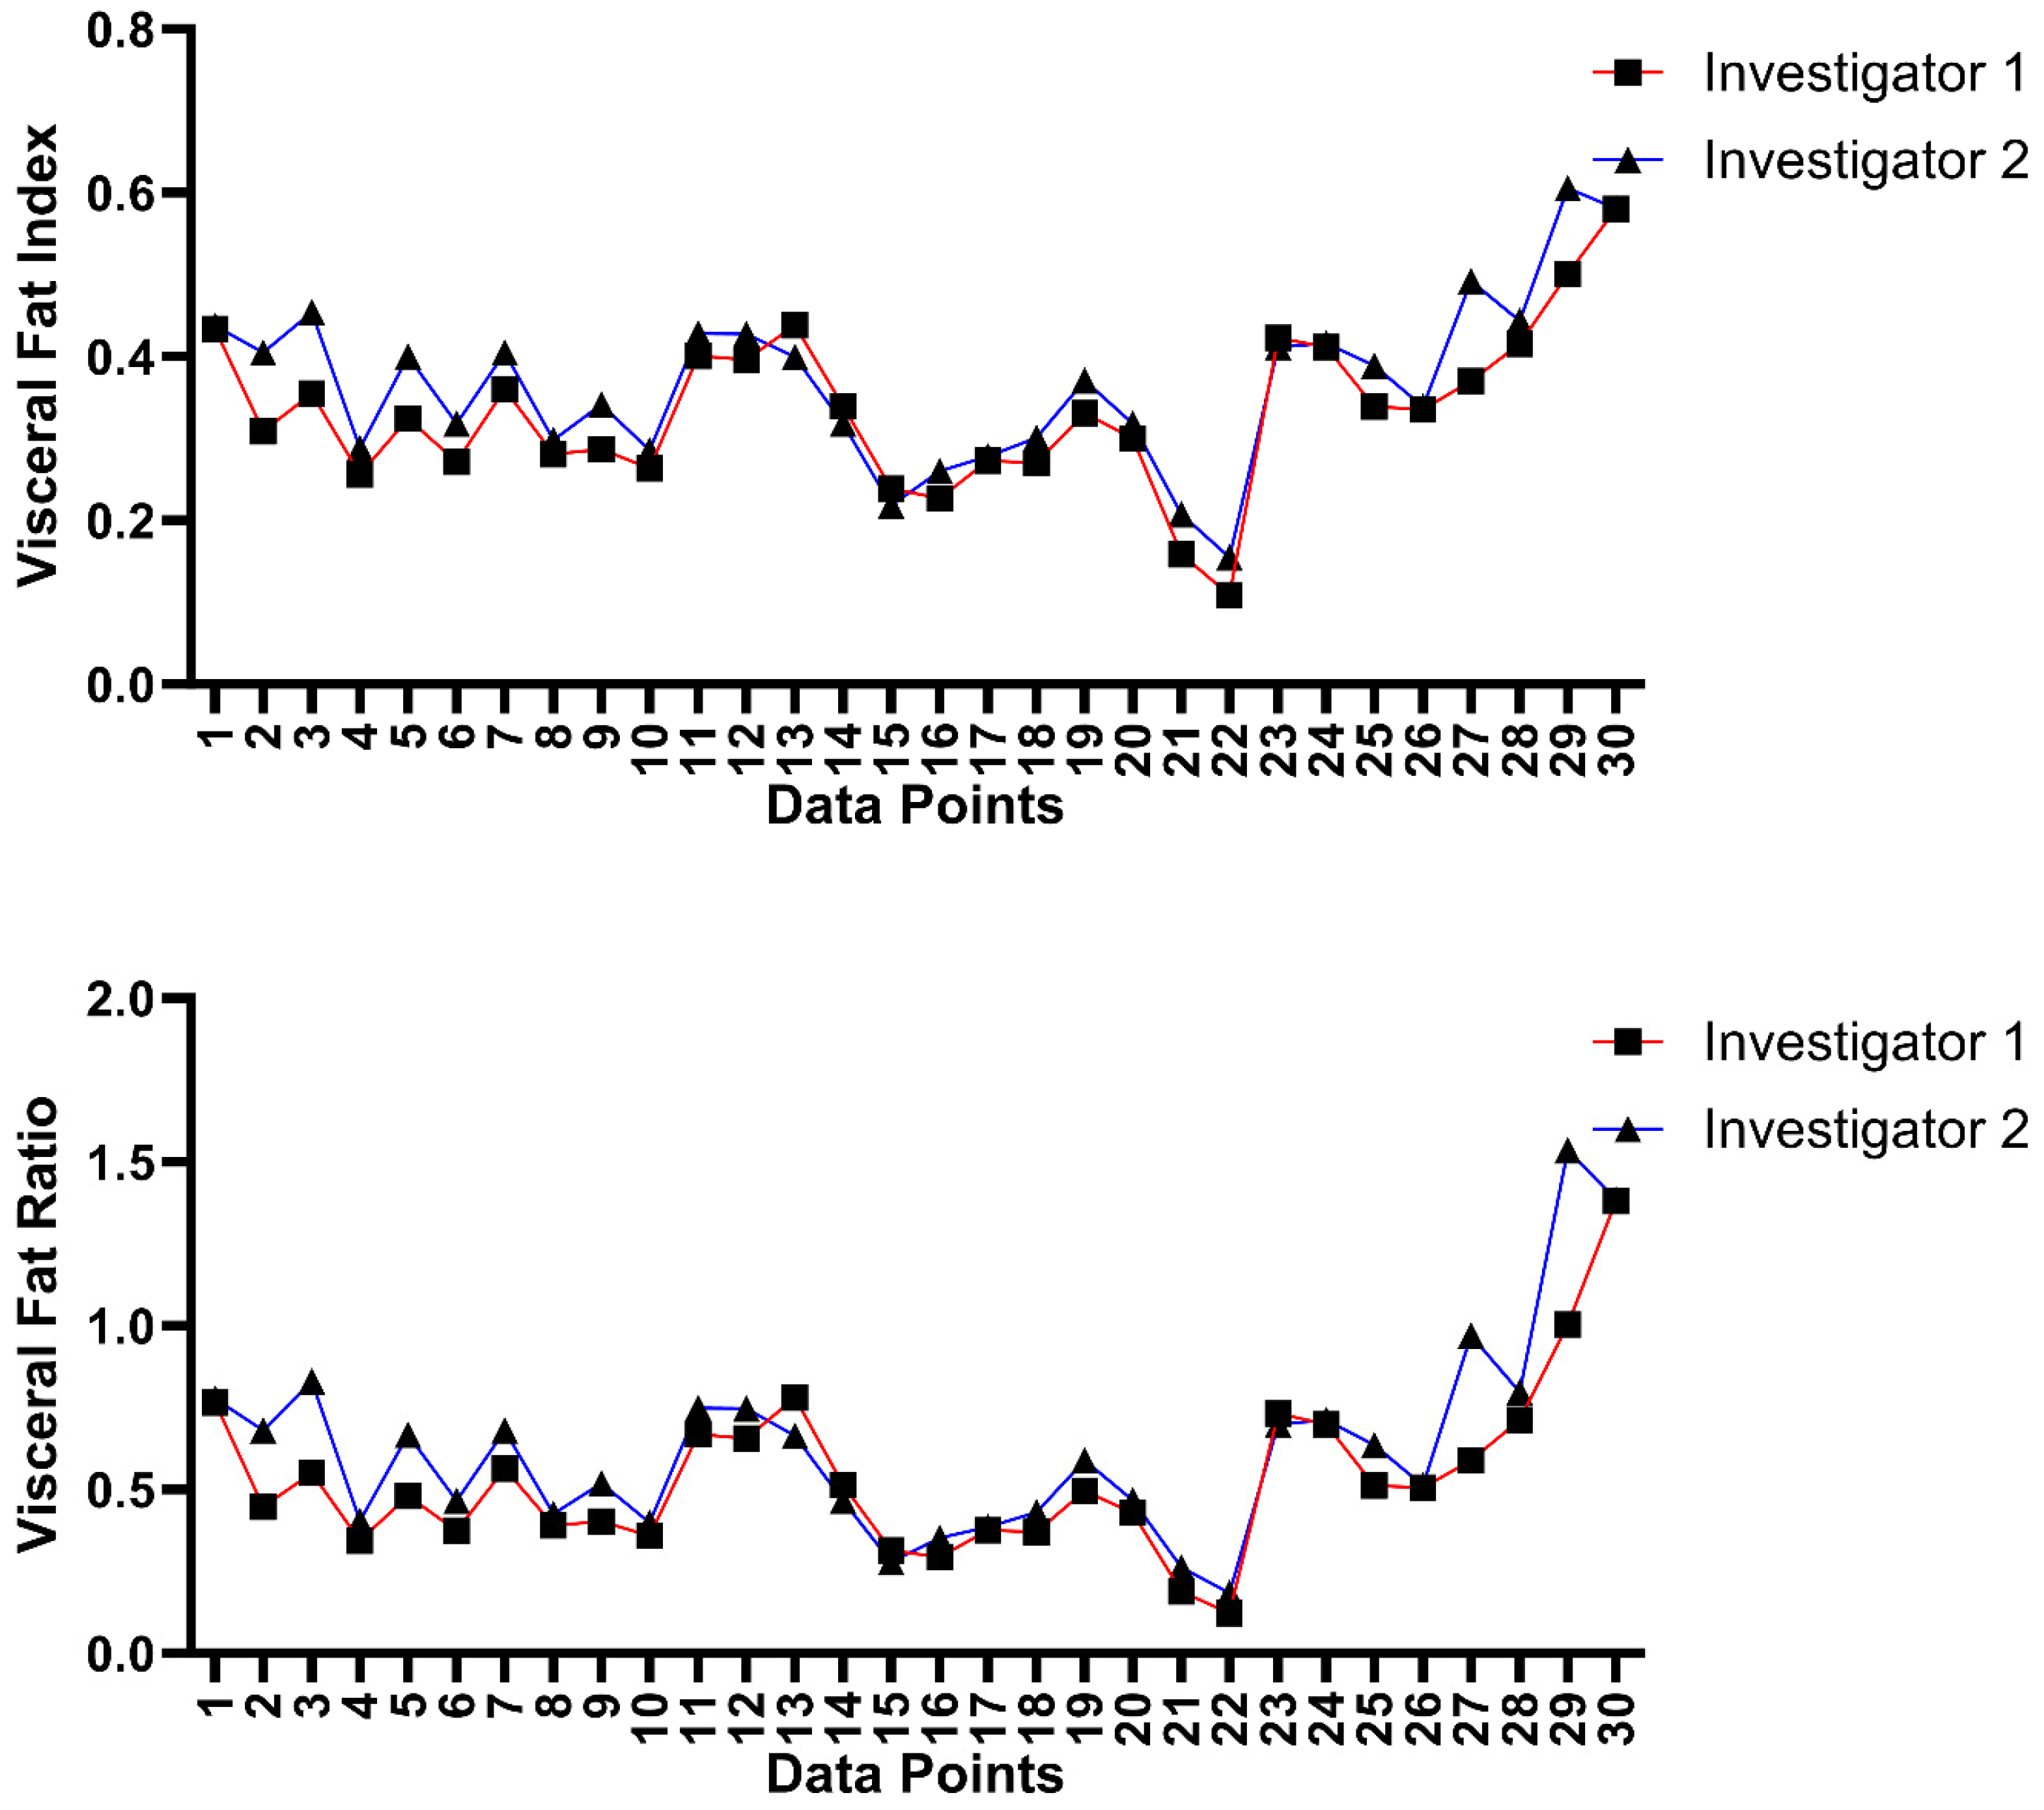

3.4. Inter-Platform and Inter-Rater Analysis